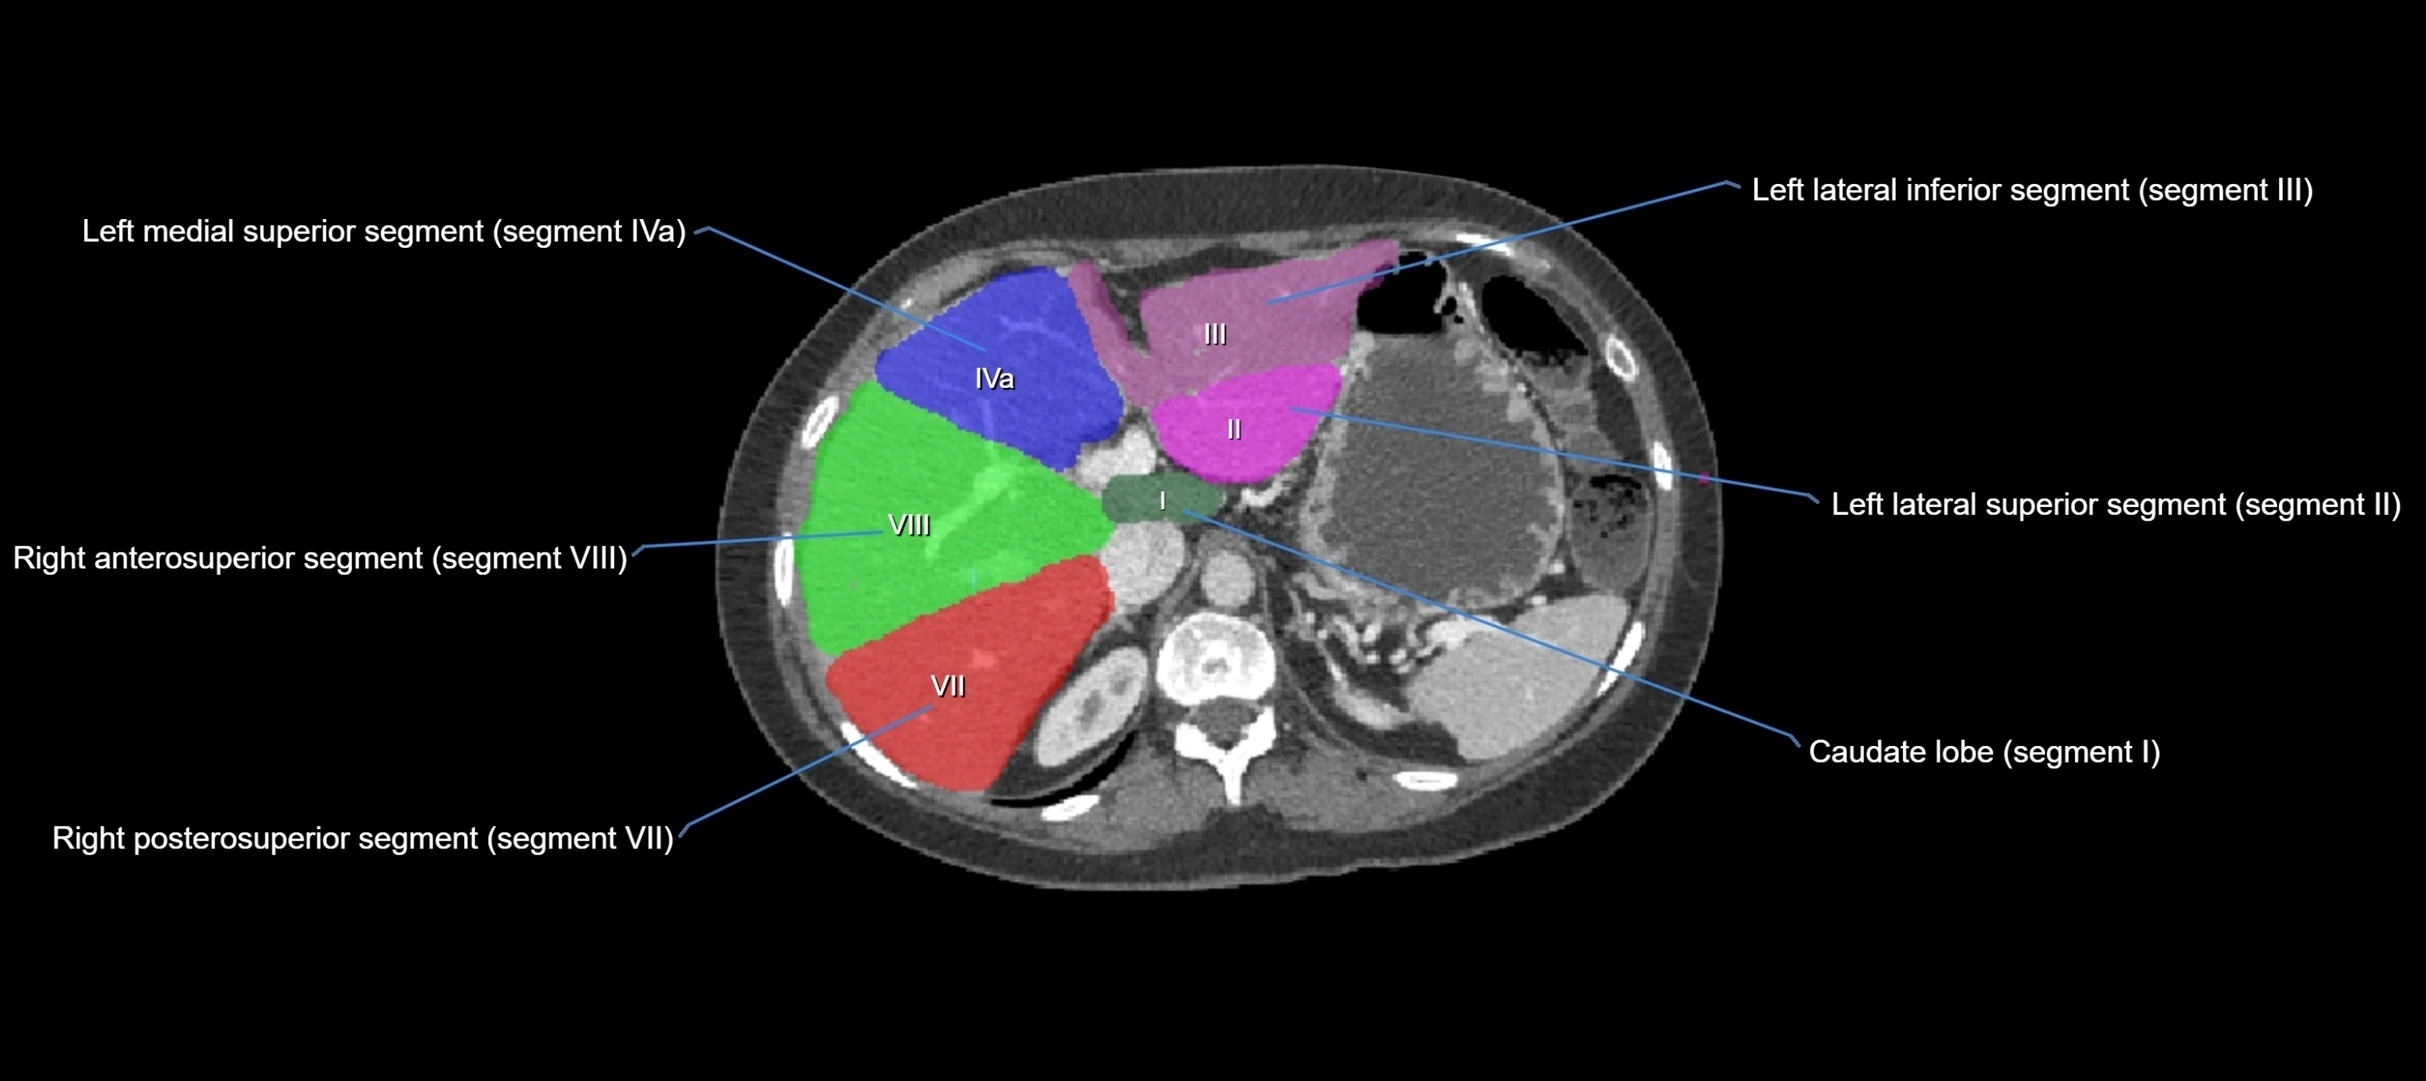

The caudate lobe of the liver is a distinct anatomical subdivision of the liver, designated as segment I in Couinaud’s classification. It lies on the posterior surface of the liver, between the fissure for the ligamentum venosum (left boundary) and the groove for the inferior vena cava (IVC) (right boundary). Superiorly, it is related to the posterior liver surface, and inferiorly it is separated from the left lobe by the porta hepatis.

CT Image

image